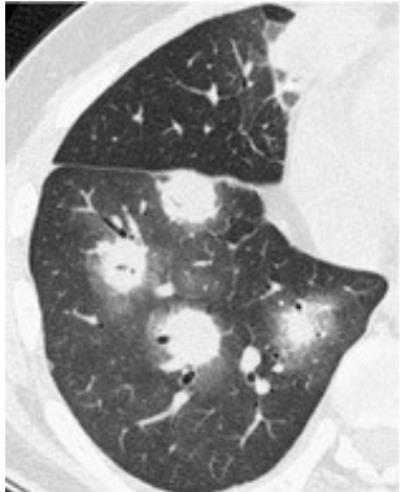

Acute Pediatric COVID-19: CT

21 Imaging of Covid 19 infection in children

3 Phases

Early: "Halo" sign

Local infection

Progressive: Diffuse GGO

Developed: Consolidation

Surr vasc congestion

Inflammation - adj alveoli

Alveoli fill with fluid/cells

Imaging of Covid 19 infection in children

Local infection Surr vasc congestion